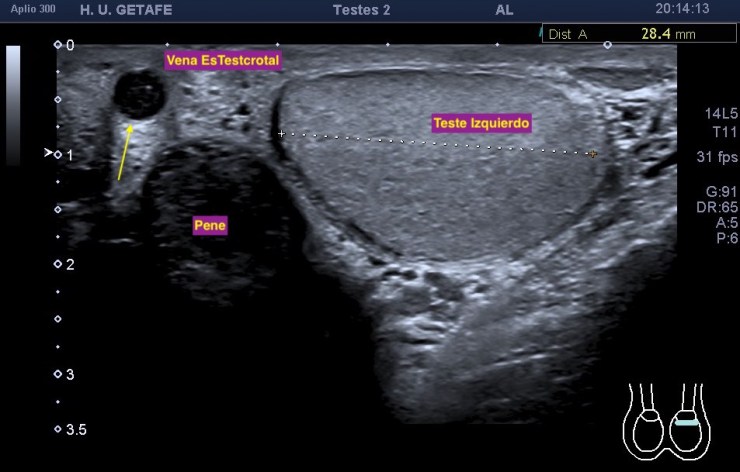

En la exploración, ambos testículos y epidídimos son de características ecográficas normales. Tiene un quiste milimétrico en cabeza del epidídimo derecho.

Repasa conmigo la anatomía en la imagen 1, te señalo el hallazgo que me llamó la atención. En la imagen 2 y 3 hay varicocele. De la 4 a la 7 el estudio dirigido al vaso central, hipoecogénico y serpenteante correspondiente a la malformación, básicamente deducido por su ausencia total de vascularización tanto en el doppler color como en el doppler power o modo angio.